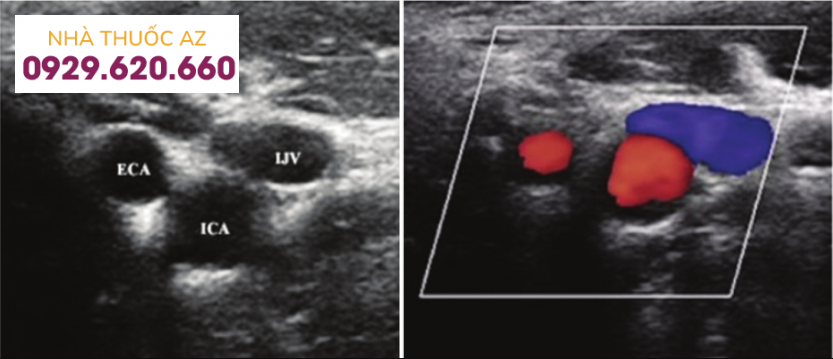

Đánh giá tổn thương trước can thiệp: Siêu âm Doppler, chụp cắt lớp điện toán đa lát cắt (MSCT) để đánh giá tổn thương

Mở đường vào động mạch: được thực hiện dưới hướng dẫn của siêu âm

Siêu âm Doppler giúp đánh giá tổn thương trước can thiệp